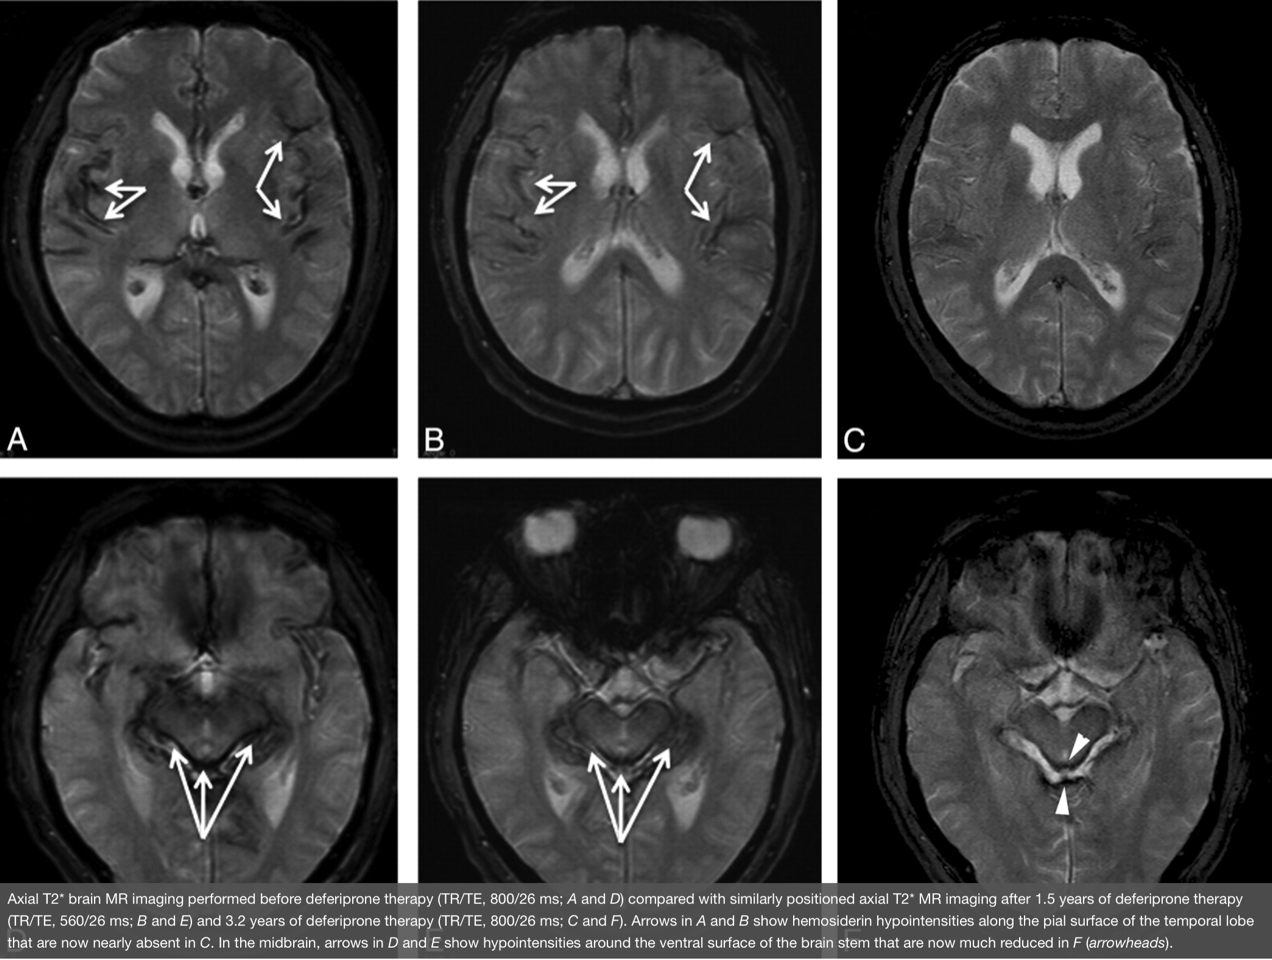

There is currently no cure for Superficial Siderosis. The only medications currently available to treat SS are oral chelation drugs, which can cross the blood-brain barrier. The best known of these medications is deferiprone (Ferriprox). Oral chelation therapy carries risks and may not be advisable for all patients. We have been testing the efficacy of deferiprone, as well as developing new MRI techniques that can assess changes in iron content in the brain.